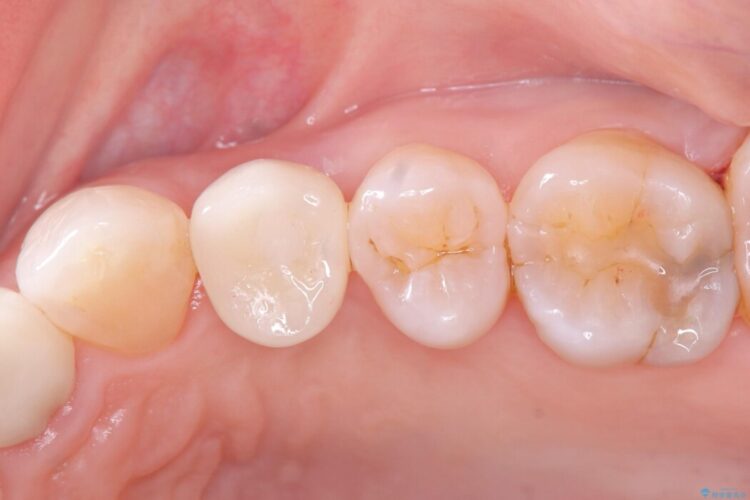

自然な見た目のセラミックインレーで精密に修復

自然な見た目のセラミックインレーで精密に修復 ビフォー 自然な見た目のセラミックインレーで精密に修復 アフター

右上5番に小さな穴があるとご相談にいらした患者様です。